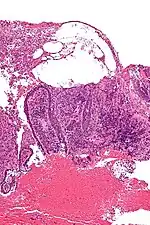

| Micrograph of pemphigus vulgaris with the characteristic "tombstoning". H&E stain. | |

Pemphigus is an autoimmune disease caused by antibodies directed against both desmoglein 1 and desmoglein 3 present in desmosomes. Loss of desmosomes results in loss of cohesion between keratinocytes in the epidermis, and a disruption of the barrier function served by intact skin. The process is classified as a type II hypersensitivity reaction (in which antibodies bind to antigens on the body's own tissues). On histology, the basal keratinocytes are usually still attached to the basement membrane leading to a characteristic appearance called "tombstoning". Transudative fluid accumulates in between the keratinocytes and the basal layer (suprabasal split), forming a blister and resulting in what is known as a positive Nikolsky's sign. This is a contrasting feature from bullous pemphigoid, which is thought to be due to anti-hemidesmosome antibodies, and where the detachment occurs between the epidermis and dermis (subepidermal bullae). Clinically, pemphigus vulgaris is characterized by extensive flaccid blisters and mucocutaneous erosions. The severity of the disease, as well as the mucosal lesions, is believed to be directly proportional to the levels of desmoglein 3. Milder forms of pemphigus (like foliacious and erythematoses) are more anti-desmoglein 1 heavy.